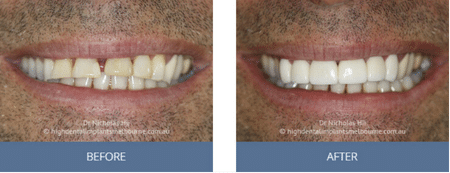

Clinical Before and After Photos

At High Dental, we believe a great smile changes everything. Our Smile Gallery showcases before-and-after images of patients who trusted us with their smiles. From veneers and crowns to full-arch implants, each result is unique — and each started with a consultation. Scroll through and imagine the possibilities for your own smile.

Images are provided for illustrative purposes only. Results shown relate to specific patients and individual outcomes may vary. A consultation is required to determine suitability for treatment.